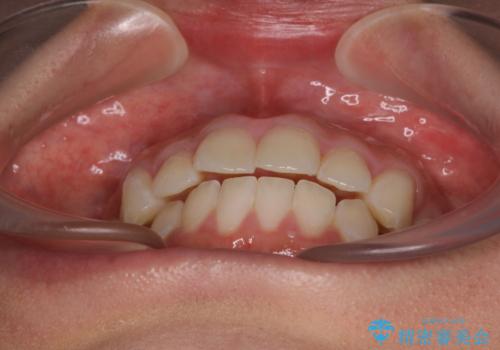

出っ歯と奥歯のむし歯 ワイヤー装置での抜歯矯正とセラミック治療

- 口元の突出感と奥歯のむし歯を気にして来院された患者様です。

奥歯の虫歯は事前に矯正治療用の仮歯に置き換えて矯正治療を行い、装置除去後にセラミッククラウンにて補綴治療を行うこととしました。

通常は上下左右の第一小臼歯4本を抜歯することになりますが、左側下顎の第二小臼歯は既に根管治療をされており、予後が良くないとのことでこの歯を抜歯し、ワイヤー装置にて矯正治療を行うこととしました。